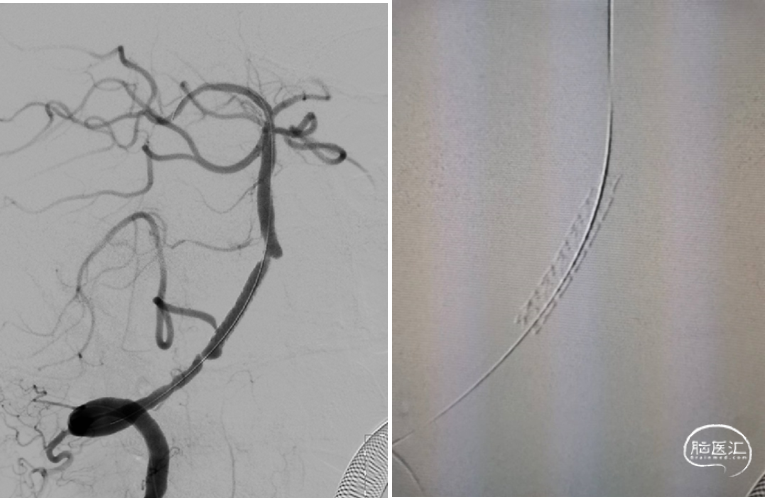

术前造影:

左椎动脉+左颈动脉造影:

右椎动脉造影:

右颈动脉造影:

右椎动脉动脉正侧位:

诊断

主要诊断:

1.右侧椎动脉V4段重度狭窄(90%);

2.高血压病2级 高危;

3.小脑梗死。

病变情况分析:右桡动脉穿刺,置6F桡动脉鞘管,5F多功能导管在泥鳅导丝辅助下脑血管造影提示:右椎动脉V4段重度狭窄(约90%)。